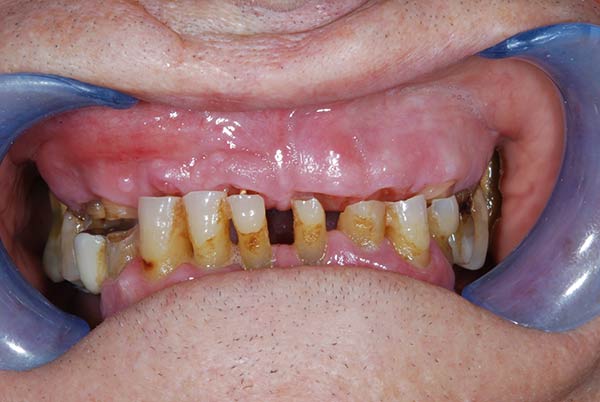

I denti irrecuperabili dell'arcata superiore ed inferiore del paziente di anni 65

sono stati sostituiti da 10 impianti, cioè protesi radicolari endo-ossee che sostengono le protesi fisse superiore ed inferiore.